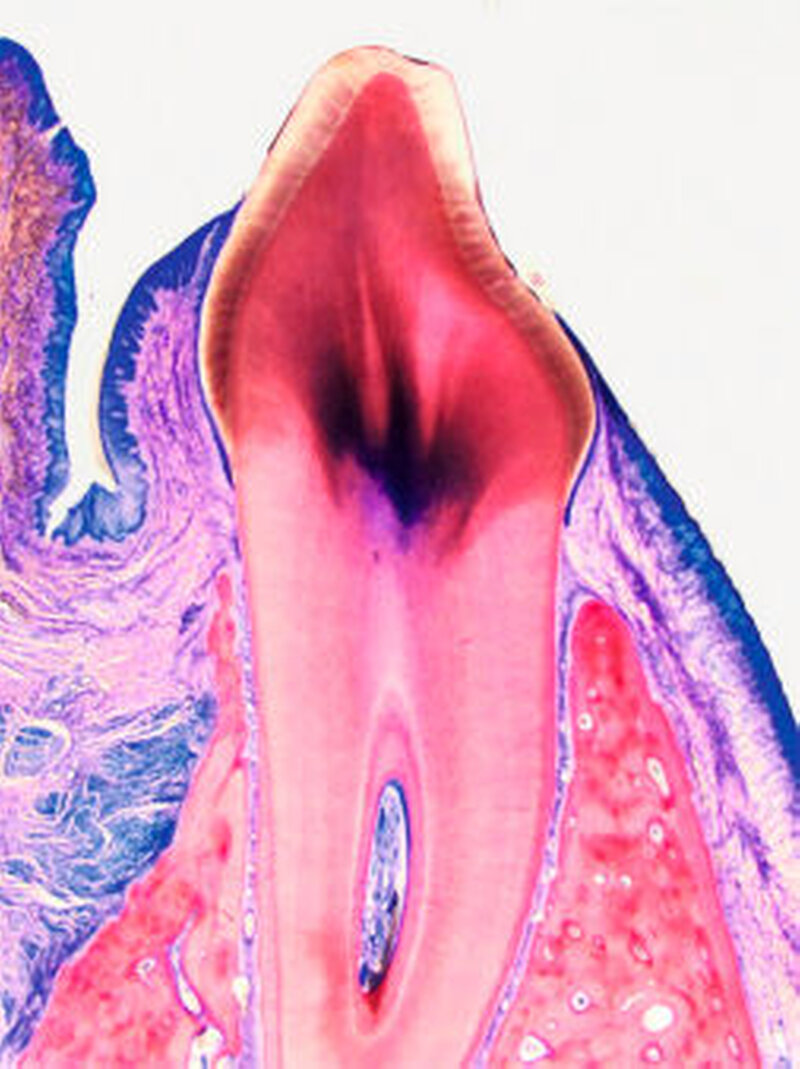

Die histologische Analyse zeigte eine Ersatzresorption sowohl der Zahnwurzel- als auch der autogenen Knochenaugmentate (Abbildung 3). Die hieraus resultierenden Kieferkammbreiten (CW) und knöchern organisierten Augmentationsflächen (AA) waren in allen Test- und Kontrollgruppen vergleichbar: Sie variierten bei den gesunden und endodontisch behandelten Zahnaugmentaten zwischen 2,70 und 2,96 mm (CW) sowie zwischen 7,55 und 11,20 mm2 (AA).

In der Kontrollgruppe (Knochenblöcke) variierten diese Werte zwischen 3,30 und 3,35 mm (CW) sowie zwischen 6,60 und 8,56 mm2 (AA) [Schwarz et al, 2016b]. Vergleichbare Ergebnisse wurden auch in der Gruppe der parodontal infizierten Zahnwurzel beobachtet (CW: 3.83 mm; AA: 10.18 mm2) [Schwarz et al, 2016c].

In den oben genannten tierexperimentellen Untersuchungen zur lateralen Augmentation chronischer Kieferkammdefekte unter Verwendung von Zahnwurzelaugmentaten wurde zudem die frühe Einheilphase enossaler Titanimplantate im Defektbereich bewertet [Schwarz et al., 2016c; Schwarz et al., 2016a]: Nach einer Heilungsphase von drei Wochen war die histomorphometrisch bewertete frühe Osseo-, beziehungsweise Dentointegration der eingebrachten Titanimplantate im Bereich der Zahnwurzelaugmentate (Mediane: 36,96 bis 50,79 Prozent) mit der im Bereich der autogenen Knochenblöcke (Mediane: 32,53 bis 64,10 Prozent) vergleichbar (Abbildung 4). Die gemessenen Werte sind mit den frühen – das heißt nach zwei Wochen – prozentualen Knochen-Implantat-Kontakten von 58,8 Prozent bis 59,3 Prozent im nativen Knochenlager grundsätzlich vergleichbar [Schwarz et al., 2007a; Schwarz et al., 2007b].